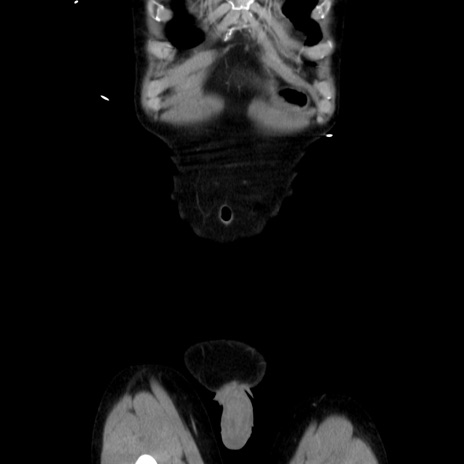

横断像